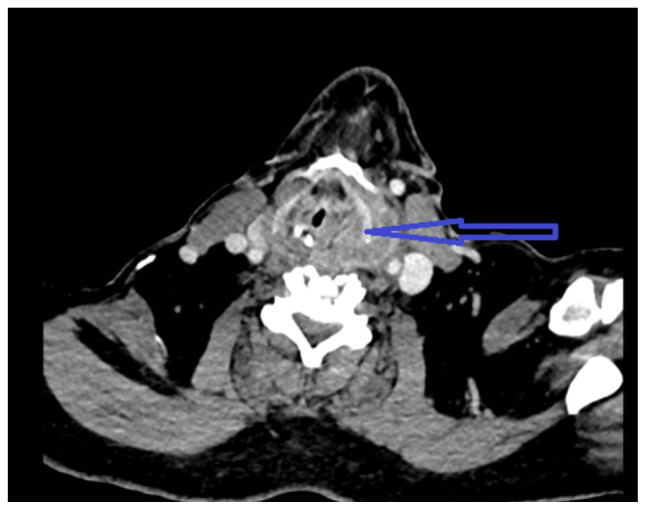

Transesophageal echocardiography is a relatively safe procedure; however, there are rare complications associated with it. Multiple attempts during TEE can lead to injury of hypopharyngeal or parapharyngeal wall leading to an infection. Here, we describe a case of hypopharyngeal-parapharyngeal abscess resulting from multiple TEE attempts during cardioversion leading to a prolonged hospital course.